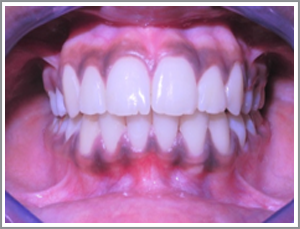

Before

After

XYZ a 14 year old girl presented with the mild protrusion of her front teeth and mild irregularity. (Angles class I mildbimaxillaryproclination and mild crowding)

Problem list : Teeth had a poor appearance due to irregularity.Lips looking too protrusive when they were closed.

Treatment plan : extraction case – case was treated with the extraction of four first premolars. The front teeth (incisors and canines) were then taken back and aligned the patient had a pleasing appearance and her lips were less protrusive.

Treatment time : 20 months